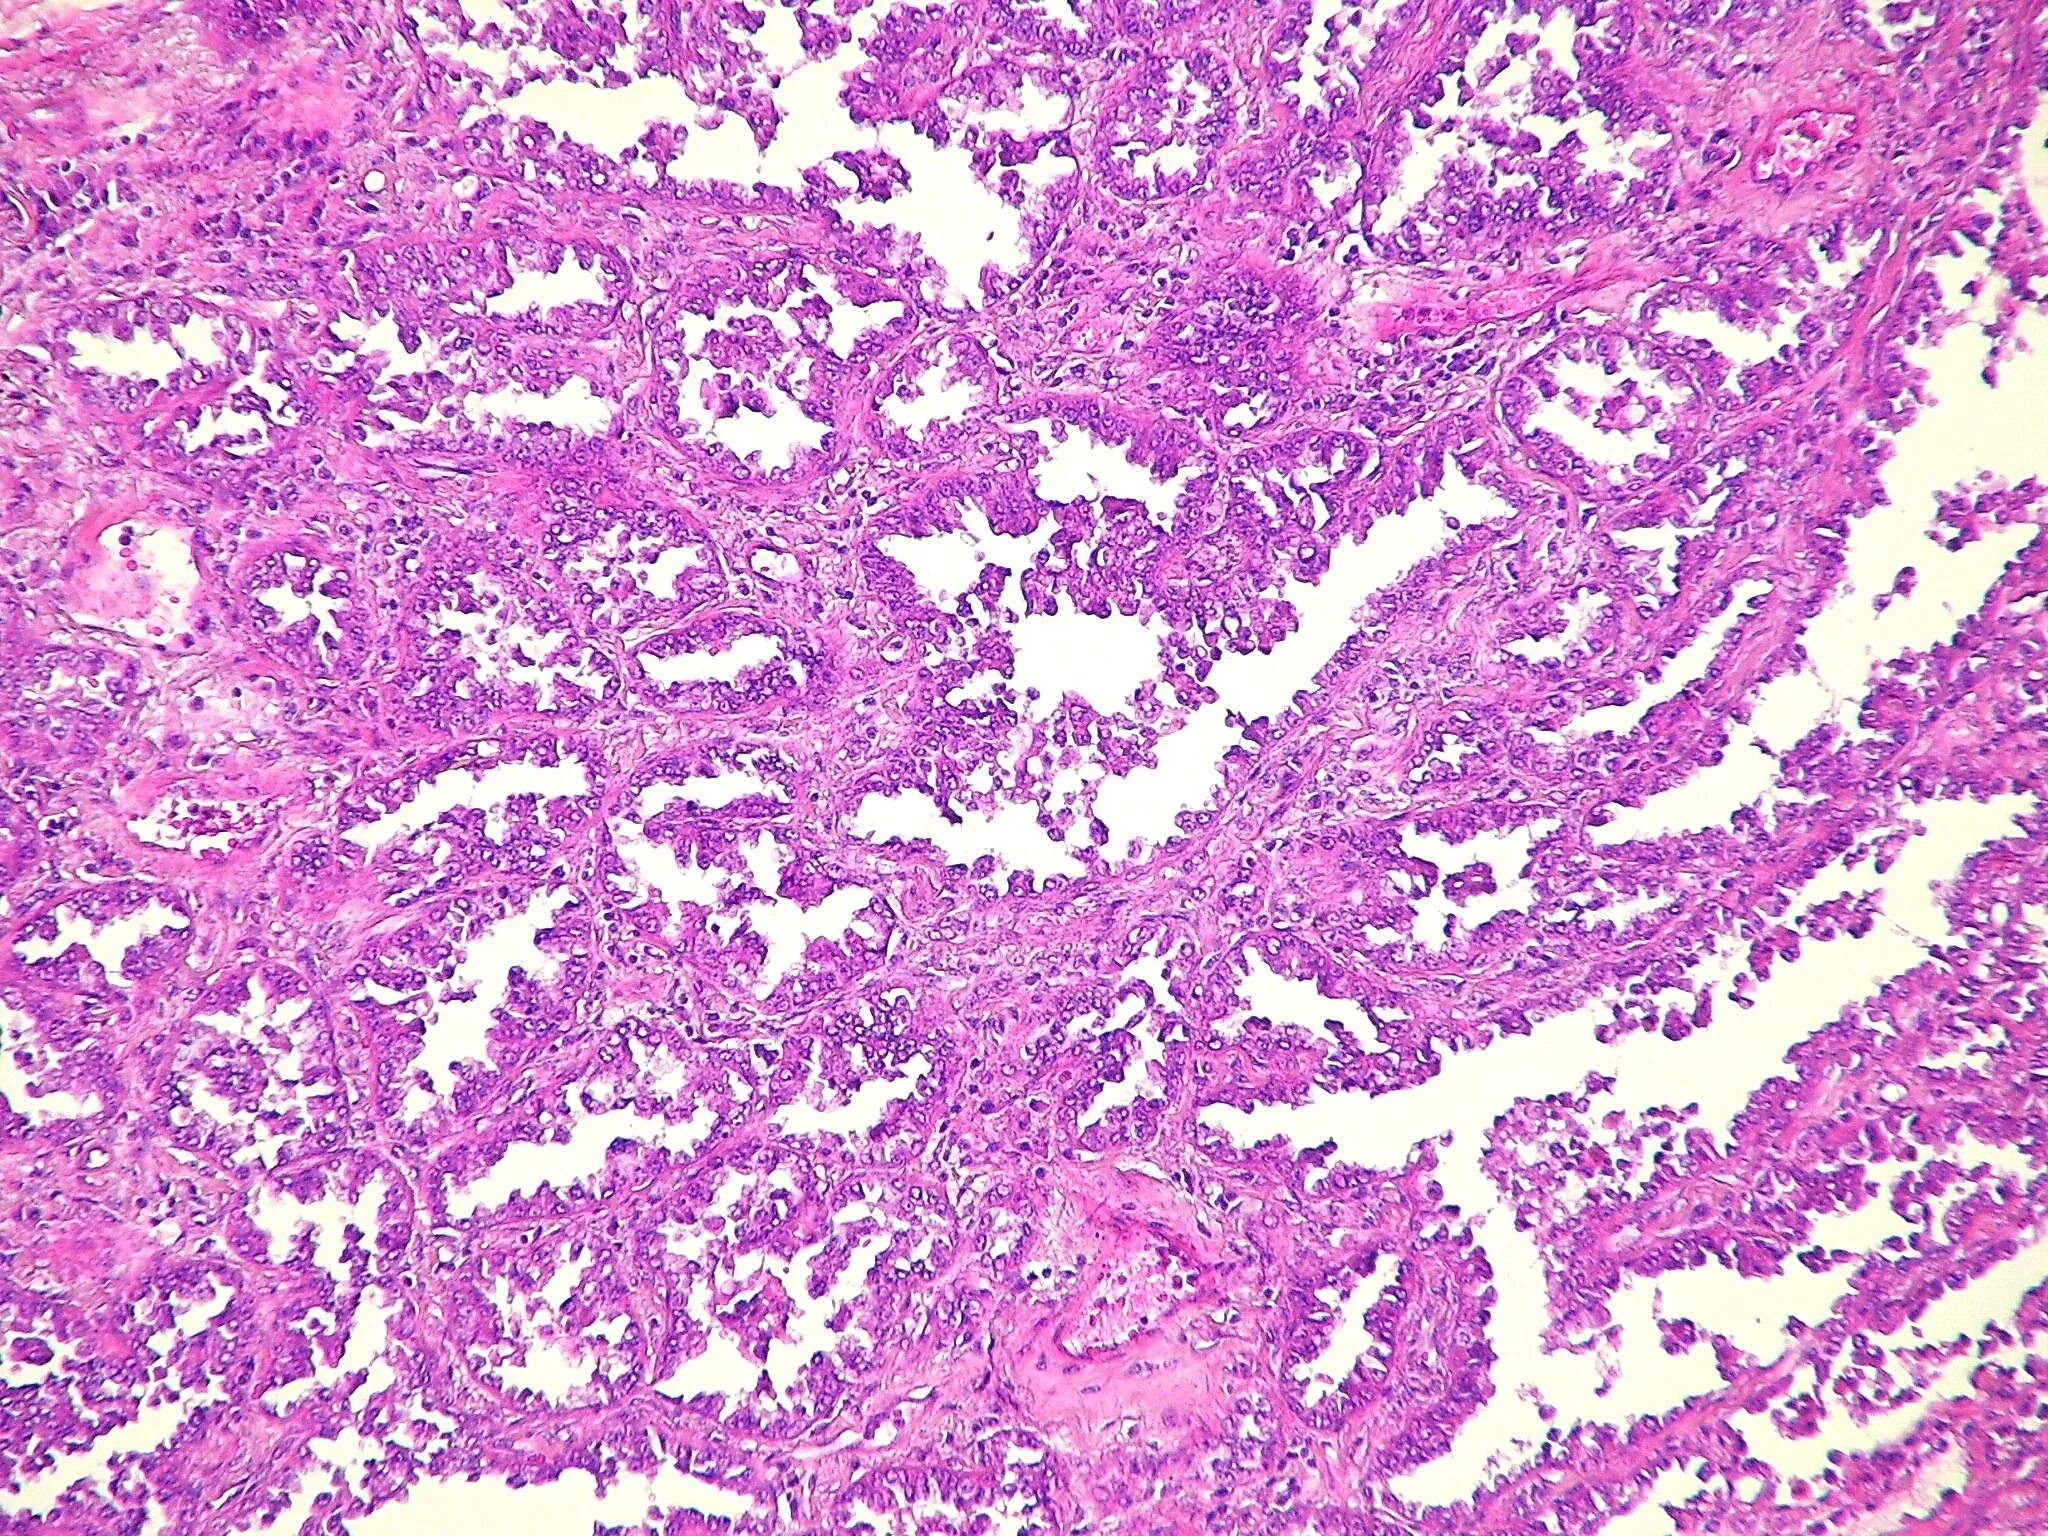

Патанат